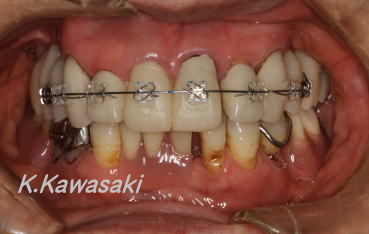

| 「前歯で物をかむことが出来ない、何とかしてほしい」と来院されました。奥歯にも虫歯が多くありました。また横顔は少し受け口でした。精密検査の結果、矯正治療後全体的に治療する事になりました。 |

| 抜歯矯正によりかみ合わせを整え、セラミックの歯を装着しました。見た目、機能の改善が出来ました。口元も美しくなりました。 |